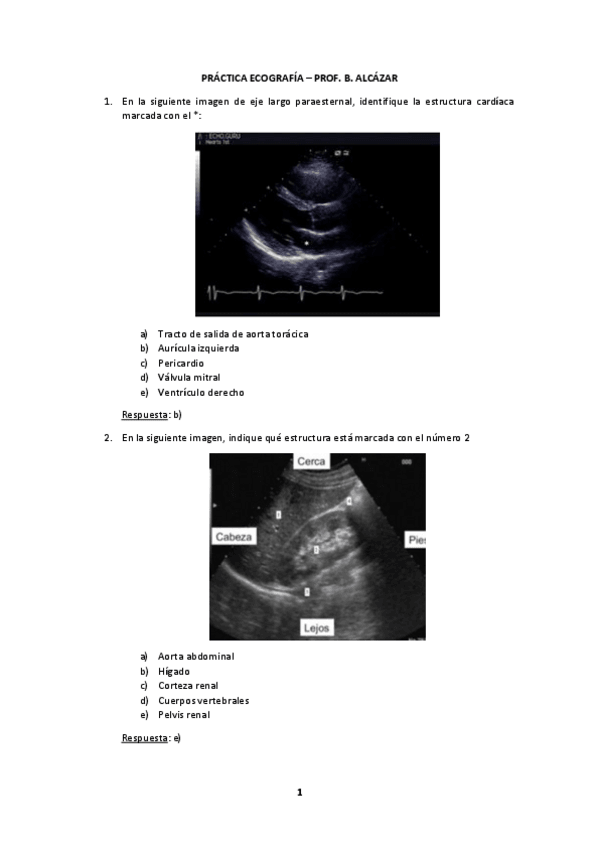

PRACTICA-ECOGRAFIA.pdf